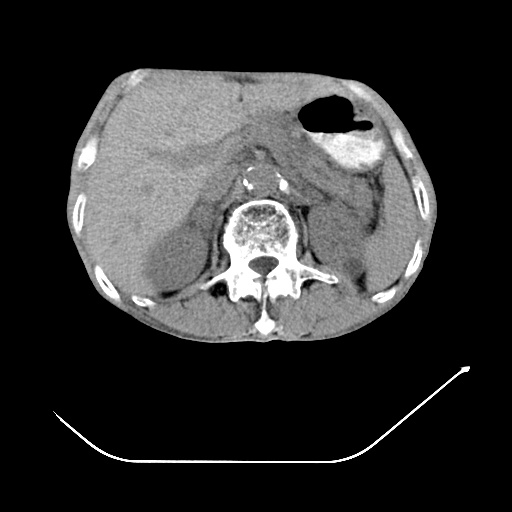

以下是引用zsl6918在2008-8-25 21:55:00的发言:[br]符合右肺周围性肺癌并肺内转移,左肺结核球。双肺肺气肿。腰椎附件转移。

以下是引用随光逐影在2008-8-25 22:03:00的发言:[br]1)考虑右肺下叶周围性肺癌并肺内转移,腰椎附件转移。2)左上肺结核(结核球形成)。3)双肺肺气肿(多发肺大泡形成)。4)双肺门区及纵隔内多发淋巴结钙化。